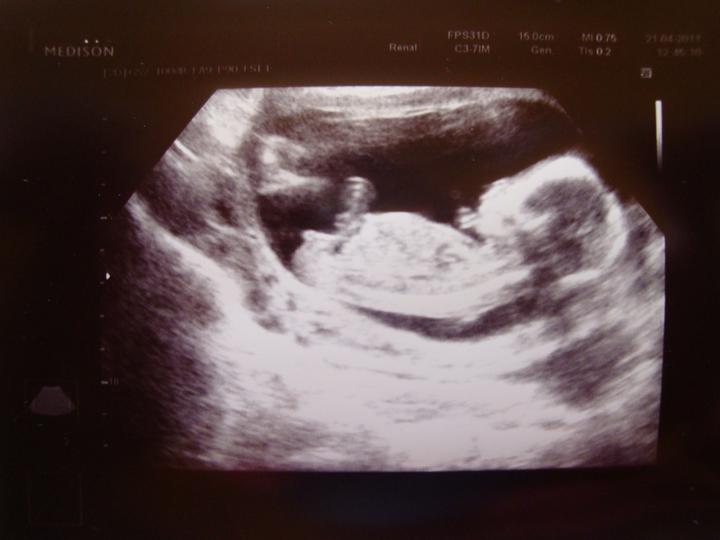

Tak zítra jdu naposledy do práce :(. Nastaly komplikace a tak mě doktorka už do práce chodit nenechá :( Ale miminko je v pořádku, a to je nejdůležitější 🙂